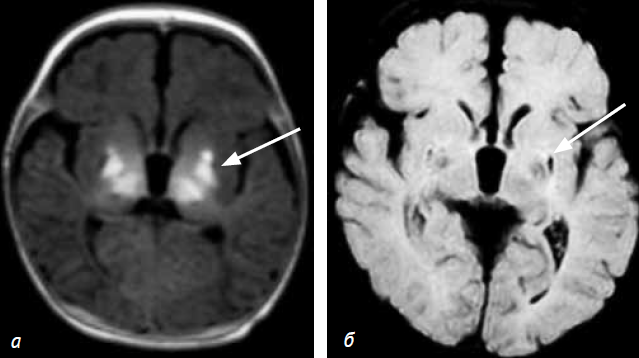

Результаты МРТ головного мозга (14-й день жизни): в области бледного шара с обеих сторон, в области скорлупы, в зонах таламусов с обеих сторон визуализируются участки повышения МР-сигнала на Т1 ВИ, Flair (рис. 4). На 3D-изображениях, полученных в результате постпроцессинговой обработки с помощью программы Fiber tracking, визуализируются участки кортикоспинальных трактов с обеих сторон, ход и направление их не изменены (рис. 5). Также отмечались повышения МР-сигнала на DWI от зрительных бугров. МРТ головного мозга у новорожденных детей контрольной группы, выполненная на 14-й день жизни, патологических изменений в головном мозге не выявила. Сравнительный анализ результатов КФА КСТ у новорожденных детей с ГИЭ и контрольной группы выявил снижение значений КФА в зоне интереса (ROI) и общего КФА КСТ при повреждении базальных ганглиев и зрительных бугров (см. табл. 1).

Рис. 4. Пациент М. МРТ головного мозга выполнена на 14-й день жизни: Т1 ВИ (а) и Flair (б). Визуализируются участки патологического усиления МР-сигнала на Т1 ВИ и Flair в области бледного шара и в зрительных буграх с обеих сторон